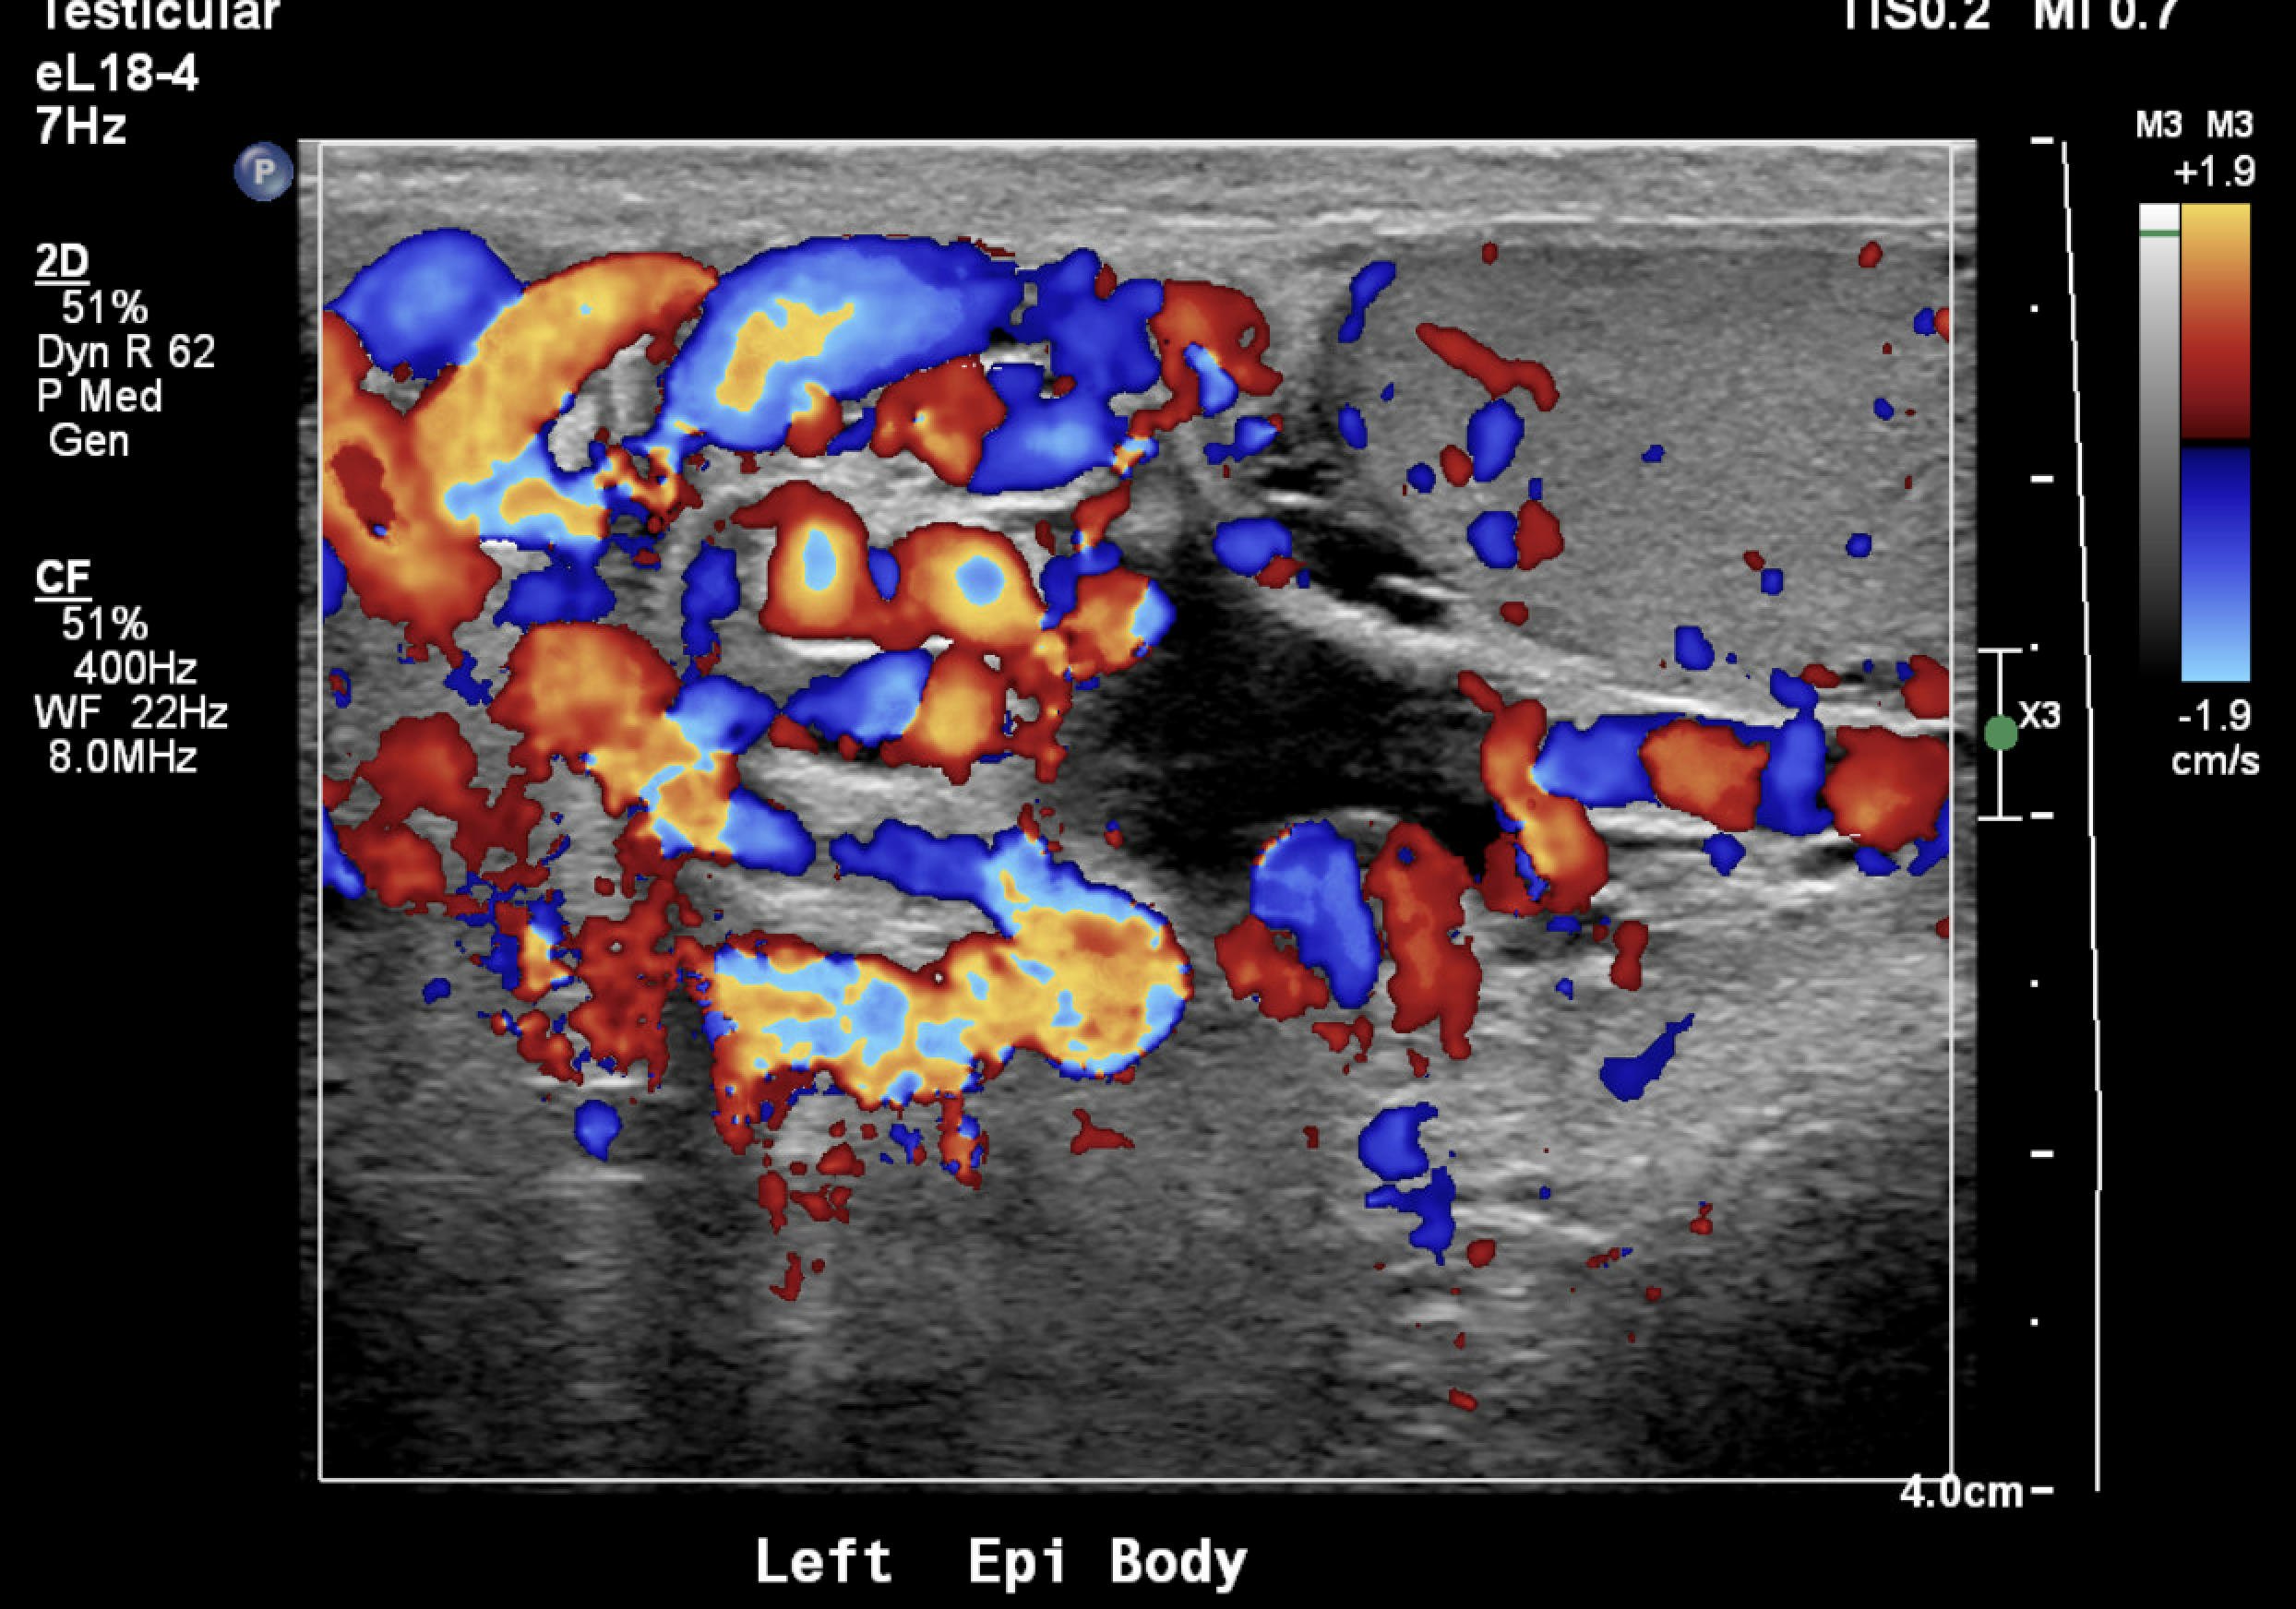

Sonographic Criteria

Pampiniform plexus veins >3 mm in diameter

Reflux >1 second on Valsalva (color or spectral Doppler)

Examination in standing position (supine alone underestimates)

Color Doppler ultrasound demonstrating dilated pampiniform plexus veins >3 mm with venous reflux — characteristic of a left varicocele.Color Doppler ultrasound showing dilated pampiniform plexus veins — venous flow confirmed on color signal without spectral waveform acquisition.